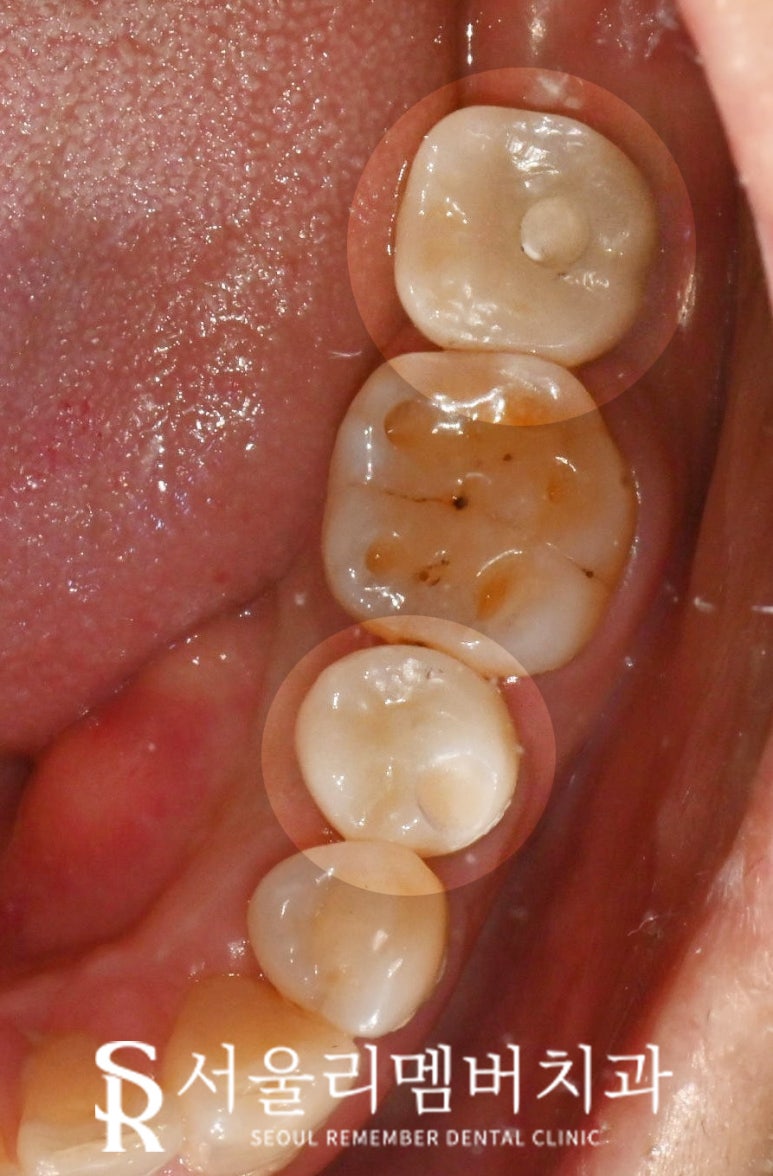

최종 보철이 장착된 모습을 보면

본래의 저작 기능을 모두 회복하였으며

임플란트의 장점인

독립적인 보철 제작이 가능하기에

사이에 치실 같은 구강위생용품 사용도 가능합니다.

올해부터 상부 보철이

PFM에서 지르코니아로 업그레이드되어

심미성과 강도를 모두 갖춘 재료로

만들 수도 있답니다.